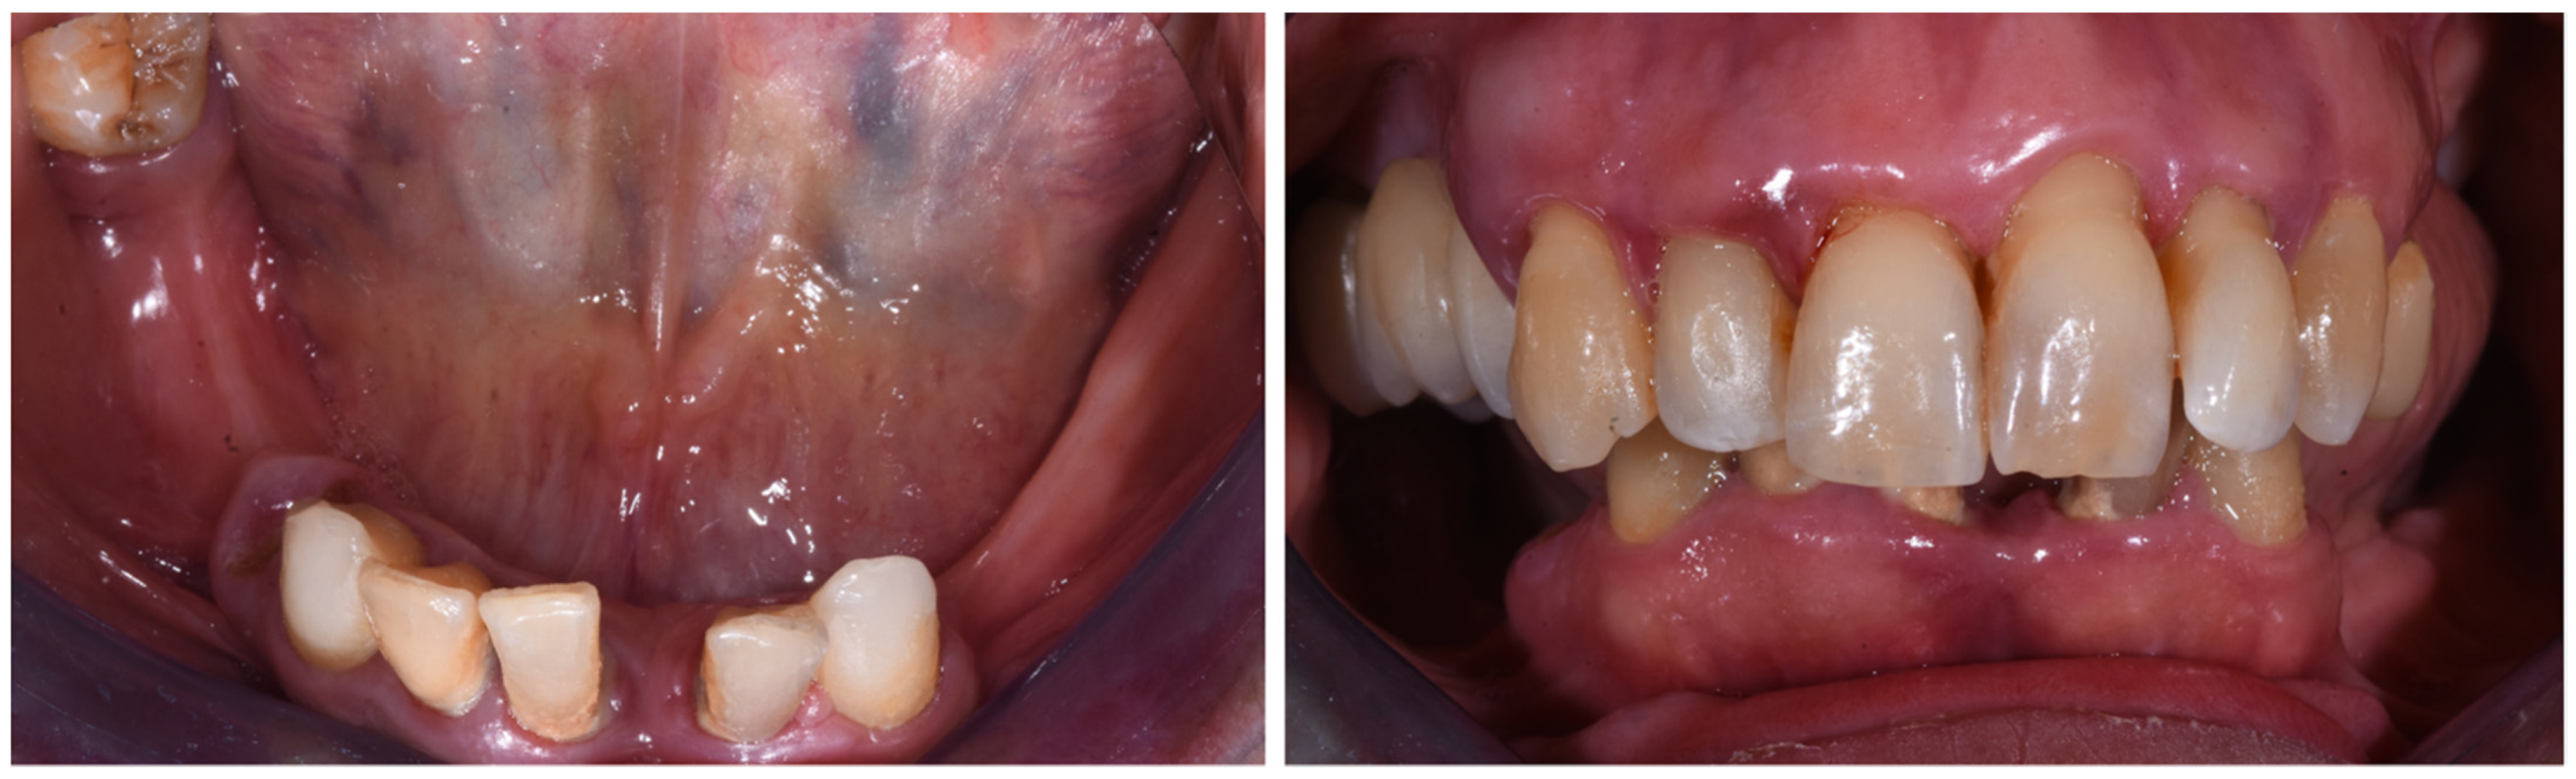

2. Case Report

Surgery Appointment